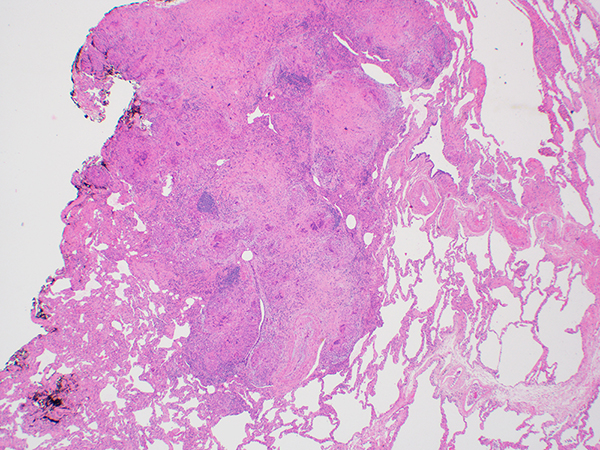

Case of the Month

Clinical History: A 64-year-old woman with worsening exertional dyspnea underwent a chest CT without contrast, which was described as showing moderate pulmonary fibrosis with probable centrilobular and paraseptal emphysema, and multiple, bilateral noncalcified lung nodules, measuring up to 1 cm. Her past medical history was most significant for severe developmental delay. She was a never smoker. A wedge biopsy of the lung was performed for evaluation of interstitial lung disease. H&E-stained sections are shown in Figures 1-5. AFB and GMS were negative (not shown). Immunostains for smooth muscle actin (SMA), estrogen receptor (ER) and HMB-45 are shown in Figure 6.

In the current case, in addition to the granulomas, there are scattered cysts, some of which show subtle, focal collections of abnormal smooth-muscle like spindle cells within the cyst walls focally infiltrating the perivascular interstitium. Upon closer inspection, the spindle cells show centrally-located, oval nuclei and variably abundant, slightly vacuolated pale eosinophilic cytoplasm. This combination of features is diagnostic of lymphangioleiomyomatosis, a diagnosis supported by the presence of immunoreactivity for HMB-45. The differential diagnosis includes benign metastasizing leiomyoma. When cystic, BML tends to show a circumferential population of atypical spindle cells, in contrast to the localized aggregates in LAM. Additionally, benign metastasizing leiomyoma is positive for SMA and ER/PR, but negative for HMB-45.

Lymphangioleiomyomatosis is a rare disorder almost exclusively affecting women and frequently occurring in the setting of tuberous sclerosis complex. Other manifestations of tuberous sclerosis include neuropsychiatric symptoms and renal angiomyolipomas. Given the history of developmental delay in this patient, the possibility of tuberous sclerosis was raised, leading to subsequent discovery of a renal angiomyolipoma. Rare case reports describe coexistent sarcoidosis and lymphangioleiomyomatosis; however, the association is likely random.

Take home message: Immunohistochemistry for HMB-45 can be helpful in establishing a diagnosis of lymphangioleiomyomatosis, particularly when the diagnosis is unexpected.